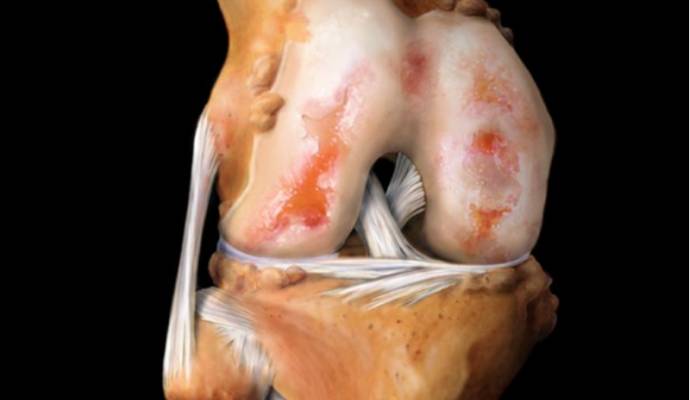

Артроз – это поражение гиалинового хряща сустава. Этот хрящ постепенно разрушается. Сначала изменяется его структура, плотность, потом он становится всё тоньше. В тяжелых случаях хрящевая ткань может полностью отсутствовать.

Третья стадия наступает при сильном разрушении хряща и является самой тяжелой. Жалобы и результаты обследования пациента с артрозом третьей стадии:

- На рентгеновском снимке видно отсутствие хряща на многих участках суставной поверхности, склероз кости. Суставная щель резко сужена, обнаруживается большое количество остеофитов.